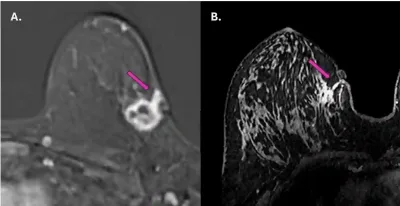

- Eine Studie aus dem Jahr 2025 untersuchte mithilfe der Magnetresonanztomographie (MRT) bei 62 Brustkrebspatientinnen, ob sich der Krebs entlang des Weges einer früheren Nadelbiopsie ausgebreitet hatte. Bei drei von ihnen (4,8 %) wuchsen Krebszellen im Biopsietrakt und erreichten teilweise die Haut und das Unterhautgewebe (Abbildung 1). Diese Befunde wurden durch Ultraschall und eine erneute Biopsie bestätigt.

Abbildung 1. Magnetresonanztomographie (MRT)-Aufnahmen zeigen die Tumorausbreitung entlang des Biopsiepfads bei zwei Brustkrebspatientinnen (violette Pfeile). In beiden Fällen scheint sich der Krebs vom ursprünglichen Tumorherd entlang des von der Biopsienadel erzeugten Pfads in Richtung Haut und umliegendes Gewebe ausgebreitet zu haben. Quelle: Fleury et al. (2025), Cureus.